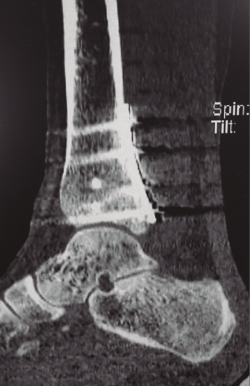

Figura 1. Tomografía computarizada que muestra fractura del maléolo posterior con pequeño fragmento intermedio.

La exploración radiológica comprende las proyecciones AP, de la mortaja y lateral (L). En la proyección AP puede observarse el flake fragment sign o spur sign, que es un doble contorno del maléolo medial, indicativo de fractura del MP con extensión al maléolo interno. La TC es fundamental para reconocer la anatomía del fragmento, su propagación medial, conminución y número de fragmentos intermedios (Figura 1).